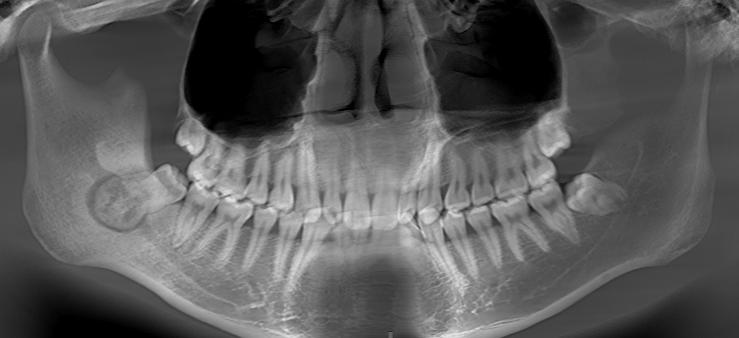

医生仔细检查后发现,张新右下方的智齿仅部分萌出,周围牙龈红肿,轻叩即痛。关键的线索藏在影像片里——CBCT检查显示,在那颗“不老实”的智齿牙根下方,紧贴着一个类圆形的高密度肿物,大小约13*14毫米。棘手的是,这个肿物与承载下唇感觉神经的下颌神经管几乎“粘”在了一起。

“这个位置很特殊,传统手术容易伤到神经,可能导致术后下唇长期麻木。”医生指着三维影像解释道。经过讨论,医疗团队决定借助动态导航辅助手术。手术当天,在如同“手术GPS”的导航系统实时引导下,医生如同拥有了“透视眼”,顺利避开了重要神经,精准地切除肿瘤、拔除智齿。术后张新恢复顺利,疼痛消失,保住了下唇的正常感觉,而病理证实为骨样骨瘤——一种好发于青少年群体的良性肿瘤。

骨样骨瘤是一种好发于青少年的良性骨肿瘤,虽多见于长骨,但也可能发生于下颌骨。其典型症状为局部疼痛,且夜间疼痛可能加重。X线或CT上常表现为边界清晰的圆形高密度影,周围可有硬化带。手术完整切除后预后良好,复发率低。